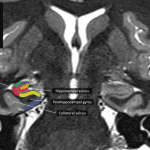

- Symmetric volume loss involving both temporal lobes and hippocampi with ex vacuo enlargement of the temporal horns of both lateral ventricles, which is out of proportion to the degree of generalized cerebral and cerebellar volume loss

Advanced bilateral temporal and hippocampal volume loss out of proportion to the over degree of cerebral atrophy, which can be seen with Alzheimer disease.

- Imaging Findings

- Atrophy (and corresponding hypometabolism on PET imaging) in the following areas:

- Mesial temporal lobes including the entorhinal cortex and hippocampus (especially CA-1) – look for disproportionate ex vacuo enlargement of the temporal horns

- Posterior cingulate gyri

- Parietal lobes (especially precuneus), sparing the primary cortex until late in the disease